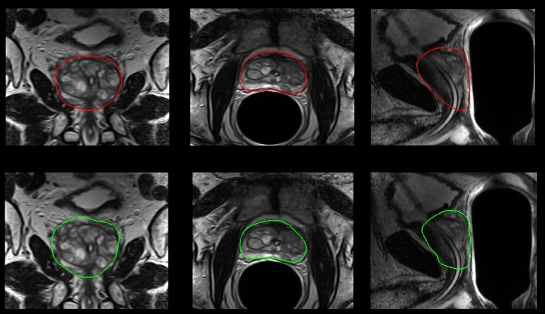

Refer to caption

Figure 4: Examples of expert and automatic segmentations : top row expert segmentations, bottom row automatic segmentations; from the left to the right coronal slice, transverse slice, sagittal slice